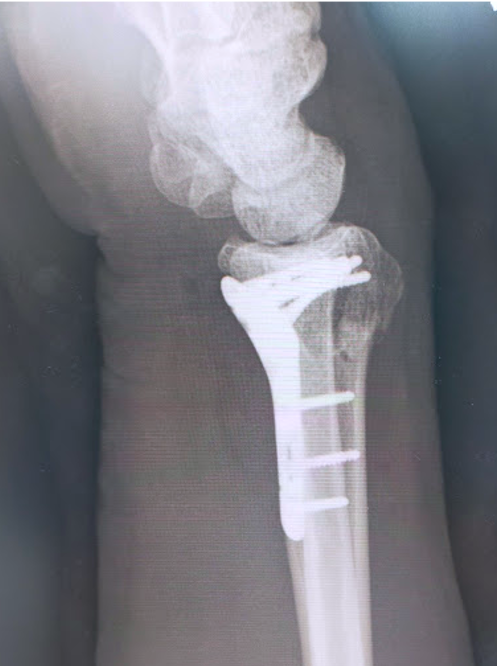

橈骨遠位端骨折に対する骨接合術